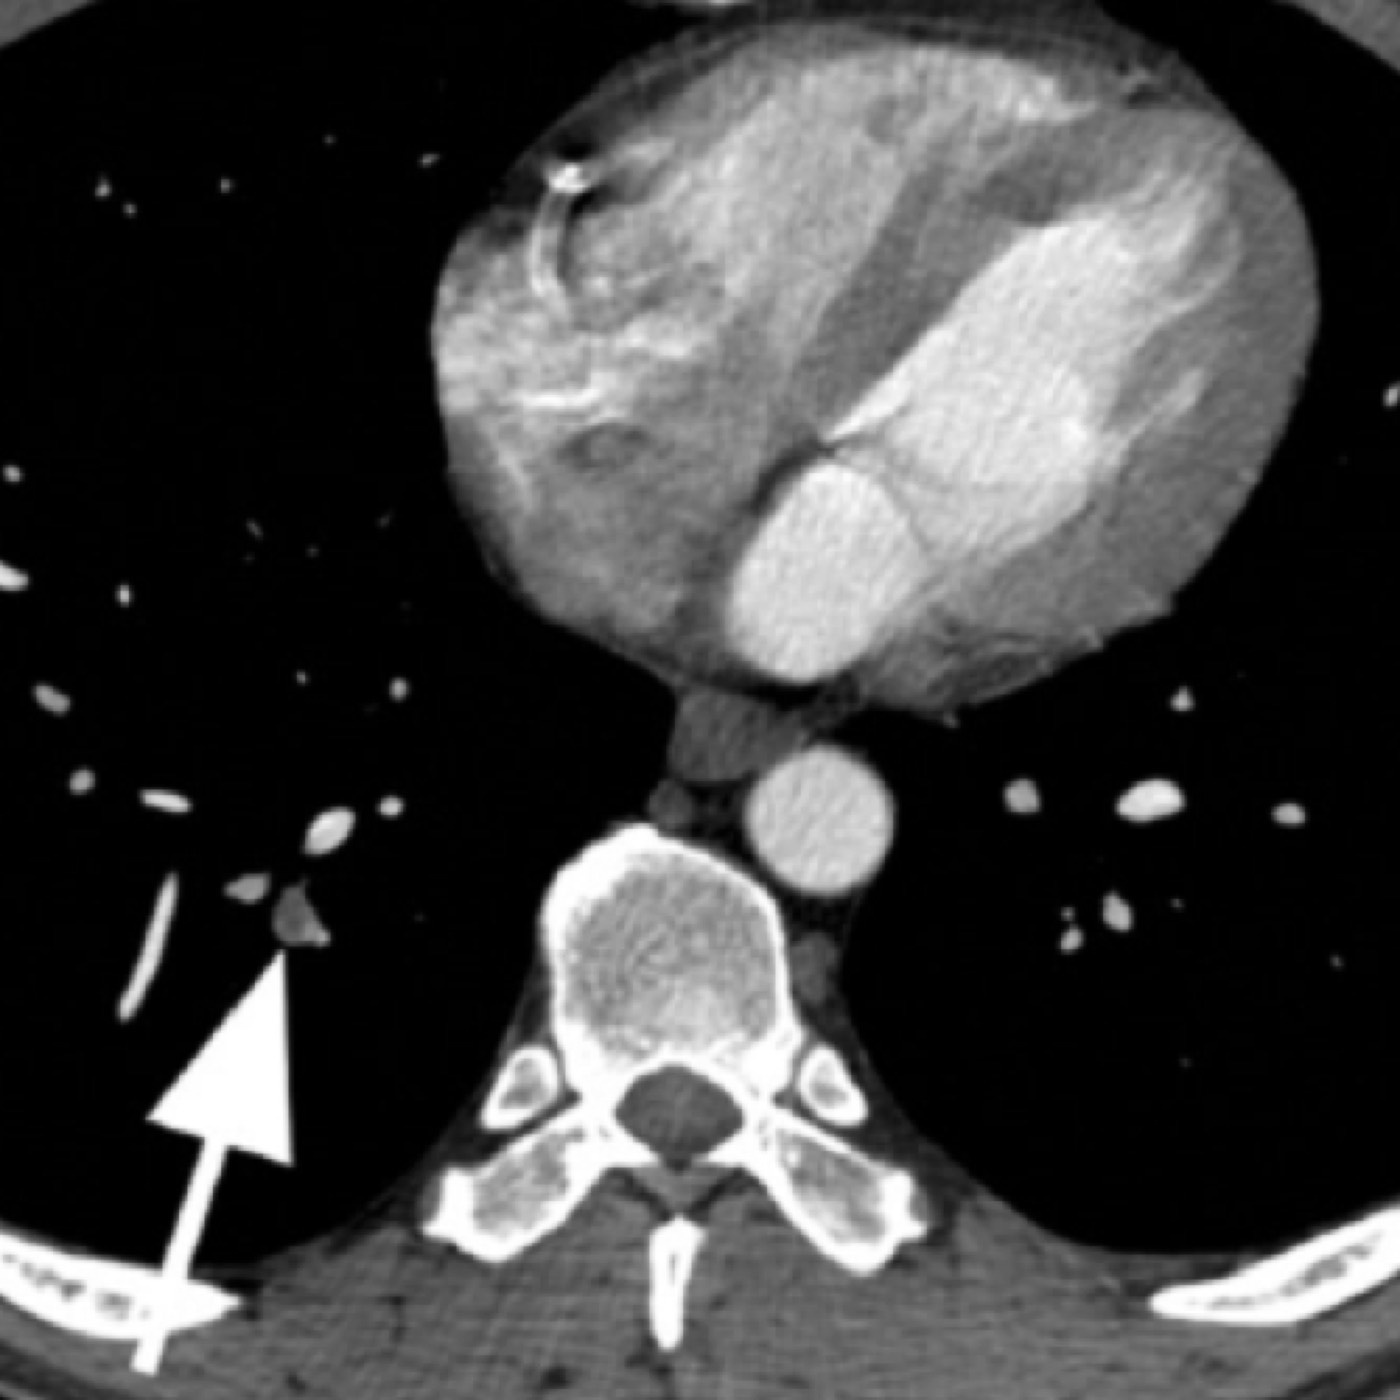

Contributors: Travis Barlock MD, Jeffrey Olson MS4 Feel free to use the cases below for your own practice. All of the scenarios are completely made up and designed to hit several teaching points. Case 1 25 M, presents to the ED with chest pain. Stabbing, started a few hours ago, substernal. Thinks it is GERD. After 2-3 minutes, pain worsens and radiates to the back. VS: BP 125/50 (Right arm 190/110). HR 120. RR of 18. Sat 98% on RA. Additional VS: Temp of 37.2, height of 6'5", BMI of 18. PMH: None, doesn't see a doctor. Meds: None FH: Weird heart thing (Mitral Valve Prolapse), weird lung thing (spontaneous pneumothorax), tall family members with long fingers and toes Physical Exam: Cards: Diastolic decrescendo at the RUSB, diminished S2. UE pulses are asymmetric, LE pulses are asymmetric, carotid pulses are asymmetric, BP is asymmetric MSK: Knees, elbows, and wrists are hypermobile. Imaging: CXR #1 normal, #2 widened mediastinum (no read yet but shows widened mediastinum), POCUS shows small effusion CTA/MRA doesn't come back until after the case. ECG: Sinus Tach Labs: NT-proBNP 500 pg/mL D-Dimer: 7000 ng/L CBC: Hemoglobin: 13.5 g/dL, WBC: 20,000/µL, Platelets: 250,000/µL Chem 7: Na 138, K, 5.7, Cl 102, Bicarb 17, BUN 45, Creatinine: 3.5 mg/dL, Glucose: 180 LFTs: Albumin 2.4, Total protein 5.5, ALP: 140, AST: 3500, ALT: 2800, TBili: 3.2, DirectBili: 2.4, Ca: 7.8 LDH: 2200 PT: 20.5, INR: 2.2, Fibrinogen: 170 5th gen High-Sensitivity Troponin: <3 Lactate: 7 mmol/L VBG: pH 7.22, paCO2 28, bicarb 15 Notes: Can have patient crash somewhere in middle and show 2nd xray Case 2: A 67-year-old female is brought to the ED by her daughter due to progressive weakness, confusion, and fatigue that have worsened over the past week. Unable to get out of bed and has become increasingly lethargic. Also having some nausea, constipation. The daughter denies any preceding illness, recent trauma, or travel. Does not know her meds but will head home to get them after talking with you. VS: BP 88/55 mmHg, HR 110, RR 20, O2 Sat 98% on room air. Additional VS: Temp 36.8°C. PMH: Hypertension, osteoarthritis, and depression. Physical exam: General: Thin, somnolent but arousable. HENT: Dry mucous membranes Neuro: Confused, A&Ox1 (self), hyporeflexia Labs (Includes many that would not return in the ED in case you want to take this case forward to the floor) CBC: WBC 9,500, Hb 16.5, Hct: 50%, Platelets 220,000 Chem7: Na 129, K 2.1, Cl 95, HCO3 34, Creatinine 1.6, BUN 40, Glucose 115 LFTs: normal Magnesium: 1.1 Calcium: 10.8 mg/dL (corrects to 12.8) iCal: 3.2 Phosphate: 2.3 mg/dL Albumin: 2 BUN:Cr ratio: 25 VBG: pH: 7.49, PaCO2 45, HCO3: 34 Lactate: 2.8 Serum Osmolality: 276 mOsm/kg (Osmolal gap of 2) Urine Osmolality: 550 mOsm/kg Urine Sodium (UNa): 10 mEq/L (low). Urine Potassium (UK): 25 mEq/L (elevated). Urine Chloride (UCl): 12 mEq/L (low). Urine Magnesium (UMg): 20 (Elevated). Urine Calcium (UCa): 50 in 24 hrs (Low) 100 cc of urine with foley FeNa Plasma renin activity: 15 mg/mL/hr (elevated), Aldosterone: 25 ng/dL (Elevated), ADH: Elevated, Diuretic screen: Positive for thiazides PTH: 8 (low), HsTrop: 32, Cortisol and ACTH: Normal. EKG: Hypokalemia features CXR: Normal Renal US: shows stones Improves with fluids Note: Can have daughter return with med list at some point including HCTZ, ibuprofen, and sertraline Case 3: Patient Presentation EMS Report: A 27-year-old male involved in a high-speed motorcycle collision is brought to the emergency department by EMS. The patient was found unconscious at the scene with evidence of severe thoracic and extremity trauma. He was intubated en route for airway protection due to altered mental status (GCS 7). VS: HR 130, BP 90/60, RR: bagging at 12 bpm, satting 88% on 100% FiO2 Primary Survey Airway: Endotracheal tube in place. Breathing: Decreased breath sounds on the left side with visible chest asymmetry and paradoxical chest wall movement. Circulation: Mottled extremities noted, with significant deformity of the right thigh. Pulses are diminished in the right leg Disability: GCS remains 7 (E1 V2 M4). Pupils equal and reactive. Exposure: Full-body examination reveals an open fracture of the right femur, multiple abrasions, and bruising over the chest wall. Vent alarms Peak Inspiratory Pressure (PIP) 40 cm H₂O (elevated) Plateau Pressure (Pplat) 35 cm H₂O (elevated) EtCO₂ (End-Tidal CO₂) 55 mmHg High-Pressure Alarm Triggering frequently Glucose 120 CBC: Hgb 8.9, Hct 27, WBC 14.2, platelets 220,000 VBG: pH 7.28, pCO2 33, bicarb 18, lactate 4.5 CXR with tension pneumothorax Patient improves after chest tube, pigtail catheter, or needle decompression. Ready to be transferred upstairs and O2 starts tanking again Vent alarms- second episode Peak Inspiratory Pressure (PIP) 35 cm H₂O (elevated) Plateau Pressure (Pplat) 30 cm H₂O (elevated) EtCO₂ (End-Tidal CO₂) 20 mmHg HR: 140, satting 84%, temp 38.5, ABG: pH 7.32, pCO₂ 30 mmHg, pO₂ 60 mmHg on 100% FiO₂, HCO₃⁻ 18 mmol/L (hypoxemia and metabolic acidosis). D-dimer: Elevated Thrombocytopenia: Platelets 90,000/µL. US shows blown right ventricle ECG shows new RBBB CT PE: Ground glass opacities, consolidation, centrilobular nodules, septal thickening, and fat-attenuating lesions. Note: Management is largely supportive care so once the diagnosis is made, end the case. References Carroll MF, Schade DS. A practical approach to hypercalcemia. Am Fam Physician. 2003 May 1;67(9):1959-66. PMID: 12751658. Coelho SG, Almeida AG. Marfan syndrome revisited: From genetics to the clinic. Rev Port Cardiol (Engl Ed). 2020 Apr;39(4):215-226. English, Portuguese. doi: 10.1016/j.repc.2019.09.008. Epub 2020 May 18. PMID: 32439107. Palmer BF. Metabolic complications associated with use of diuretics. Semin Nephrol. 2011 Nov;31(6):542-52. doi: 10.1016/j.semnephrol.2011.09.009. PMID: 22099511. Reed MJ. Diagnosis and management of acute aortic dissection in the emergency department. Br J Hosp Med (Lond). 2024 Apr 30;85(4):1-9. doi: 10.12968/hmed.2023.0366. PMID: 38708978. Roberts DJ, Leigh-Smith S, Faris PD, Blackmore C, Ball CG, Robertson HL, Dixon E, James MT, Kirkpatrick AW, Kortbeek JB, Stelfox HT. Clinical Presentation of Patients With Tension Pneumothorax: A Systematic Review. Ann Surg. 2015 Jun;261(6):1068-78. doi: 10.1097/SLA.0000000000001073. PMID: 25563887. Rothberg DL, Makarewich CA. Fat Embolism and Fat Embolism Syndrome. J Am Acad Orthop Surg. 2019 Apr 15;27(8):e346-e355. doi: 10.5435/JAAOS-D-17-00571. PMID: 30958807. Produced by Jeffrey Olson, MS4 Special thanks to Evan Fisch MD Get your tickets to Tox Talks Event, Sept 11, 2025: https://emergencymedicalminute.org/events-2/ Donate: https://emergencymedicalminute.org/donate/